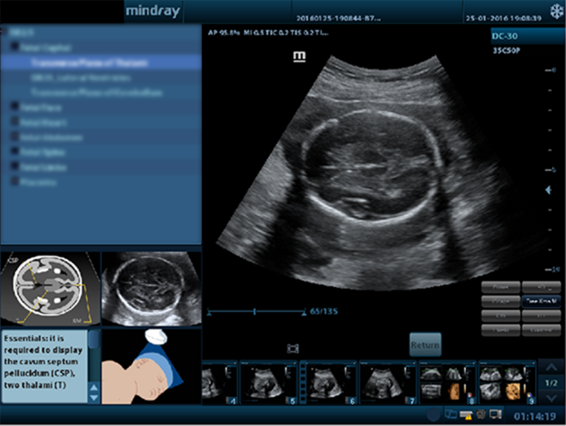

Standard ultrasound systems available today typically allow for a basic diagnosis but lack advanced functionality. Now, the DC-30 FullHD is the perfect answer for high quality image performance, with 21.5 inches Full HD LED Monitor and advanced function such as Auto IMT, iScape, Natural Touch Elastography, UWN Contrast Imaging and Tissue Doppler Imaging in General Imaging and Smart OB, Smart face and iLive in OB.

-Higher Reliable Dependence: iScanHelper

Mindrayโs GI solution in primary care

-DC-30 with FullHD delivers a range of tools that maximize diagnostic accuracy with convenience. Covering General Imaging, OB/GYN, DC-30 with FullHD provides you with a complete solution for mainstream clinical applications, with simplified workflow for efficiency.

Mindrayโs OBG in primary care

-Smart OB provides accurate auto measurements for most frequently examined fetal parameters including BPD, OFD, HC, AC and FL.